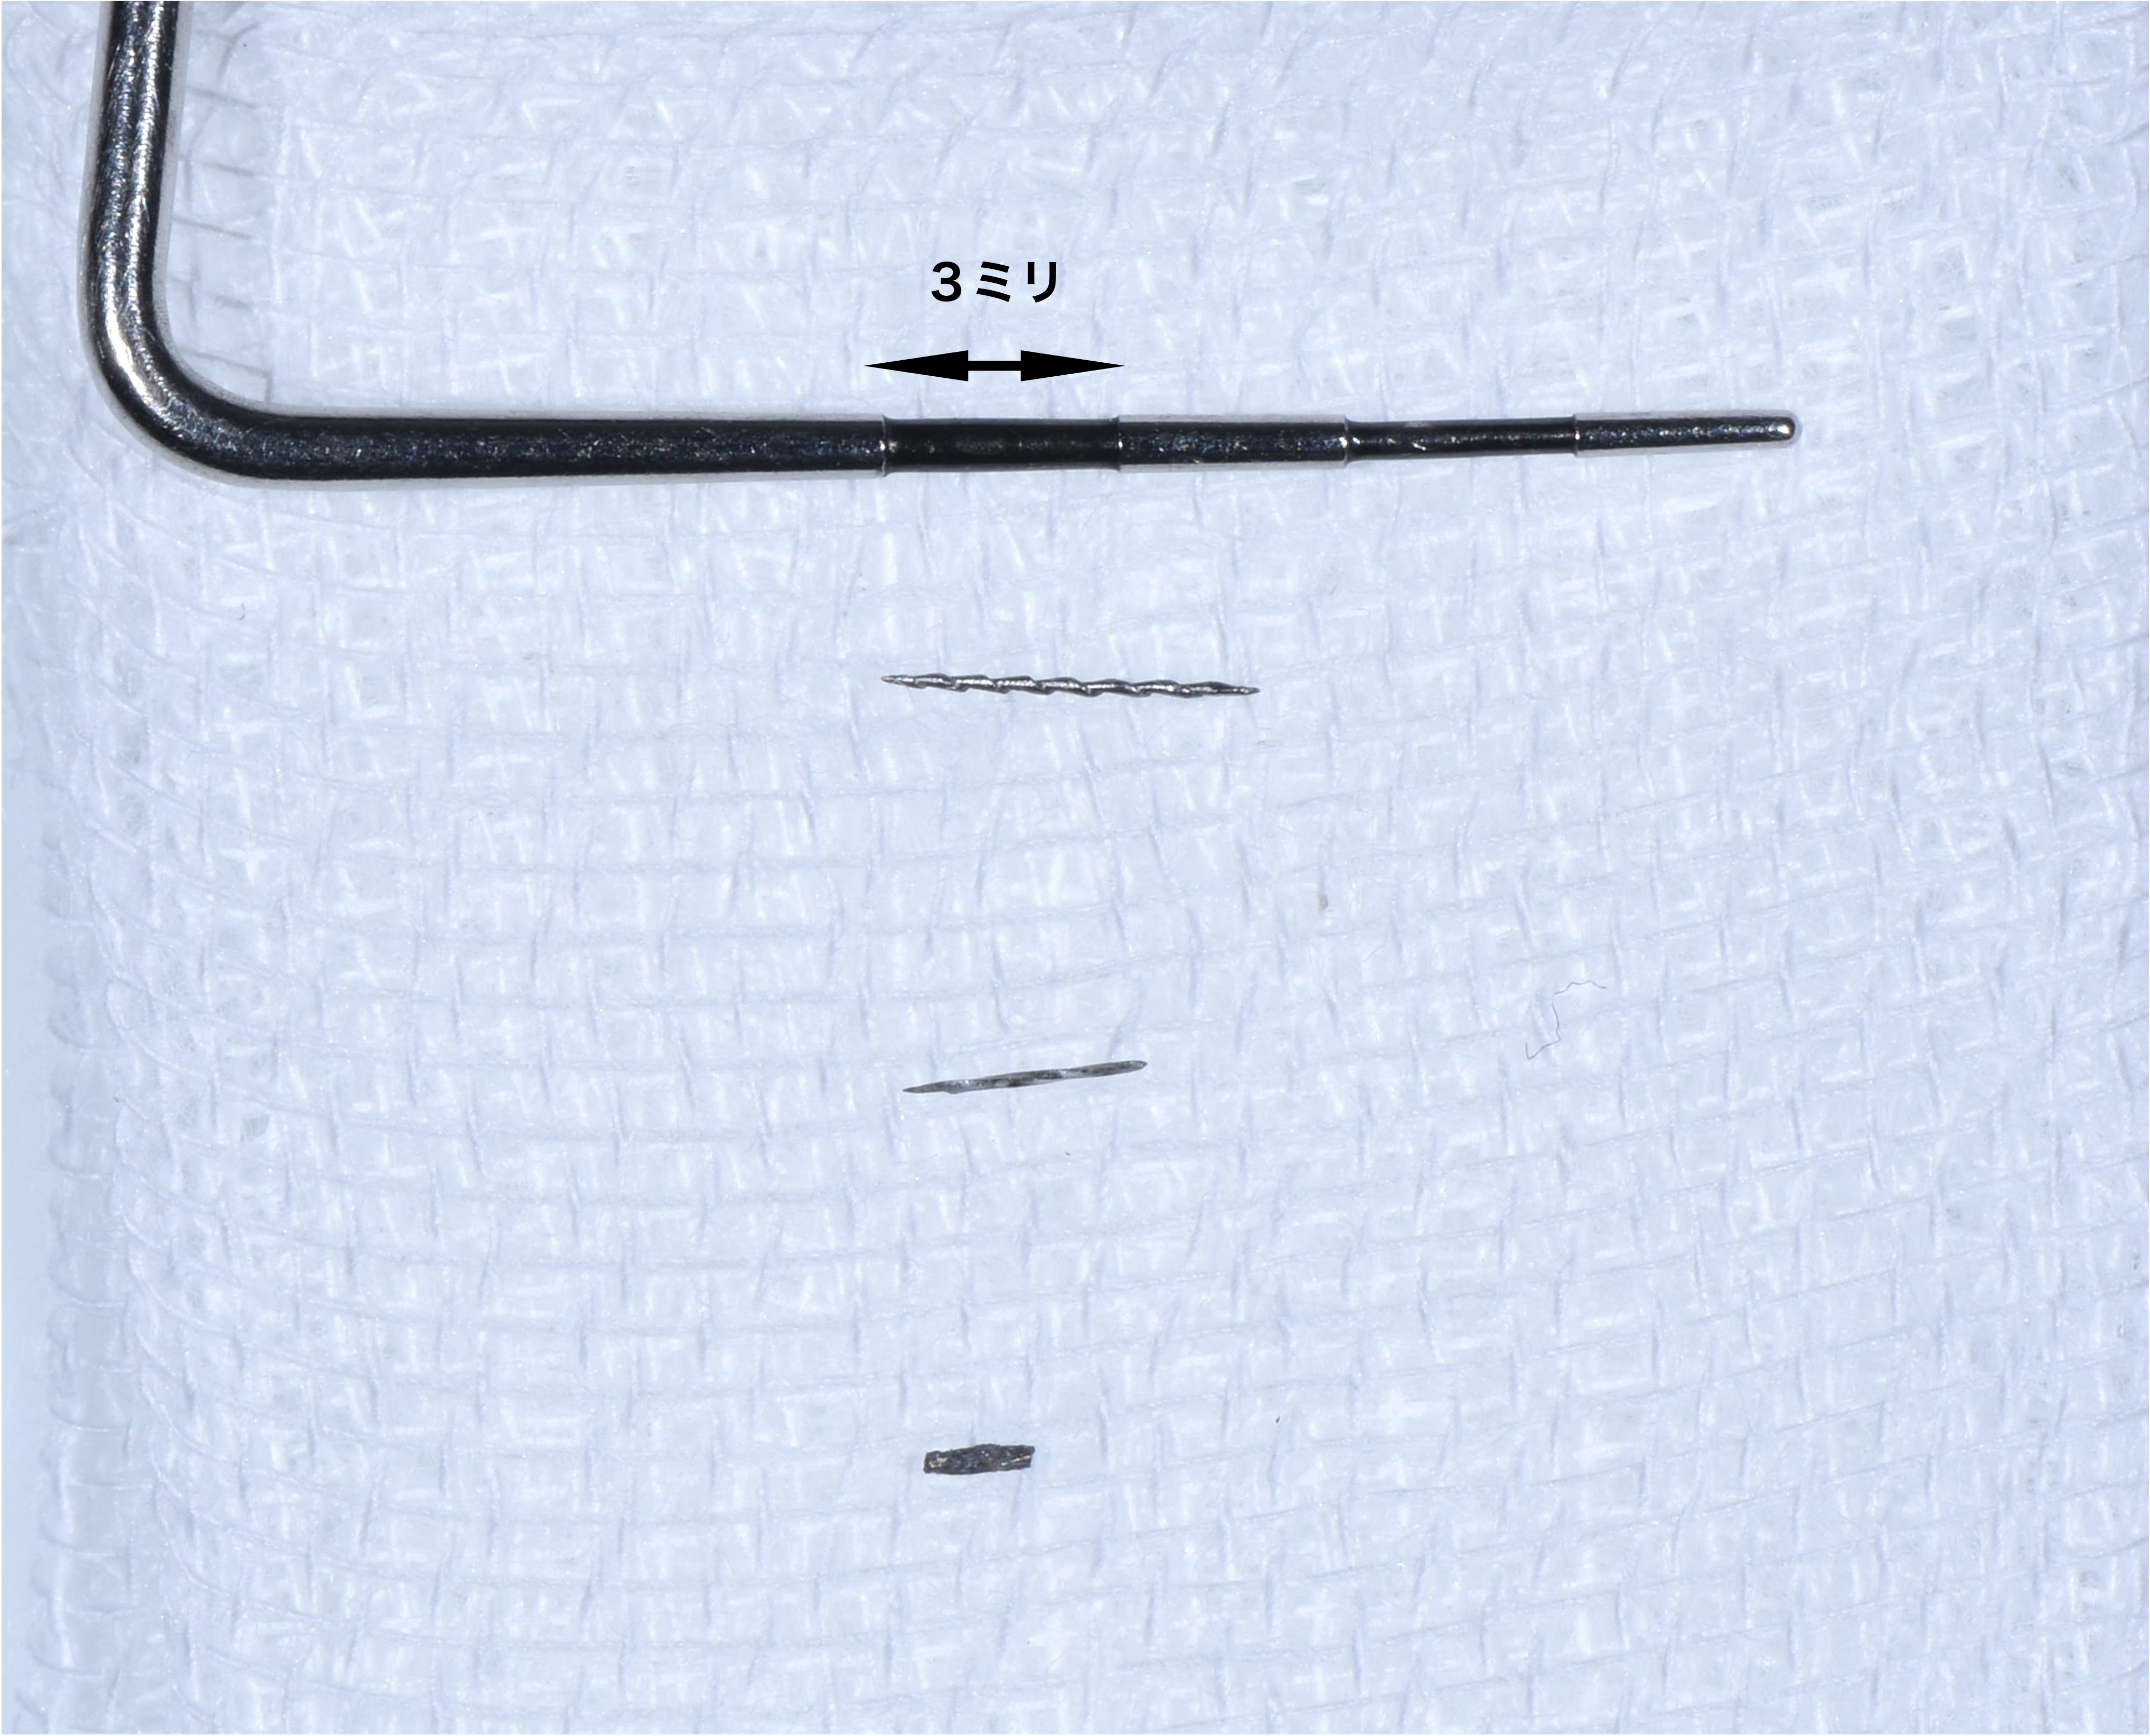

今回歯の上部は健全な部分がたくさん残っているので、上から直径3ミリほどの小さな穴を開けそこから、根の内部の吸収部を除去しようと試みました。

そこで肉芽を様々な器具や技で除去をし、出血を止め薬剤で消毒しました。

言葉で書くのは簡単ですが、これには非常に時間がかかりとても困難な治療でした。そこにMTAセメントを用い、根の先端の方(赤矢印)と吸収部(黄色矢印)を同時に埋めました。